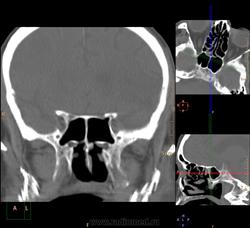

Вроде основных две, но разнообразные перегородки делят их на бОльшее количество:

Тут, например, 7 камер у одной пациентки: